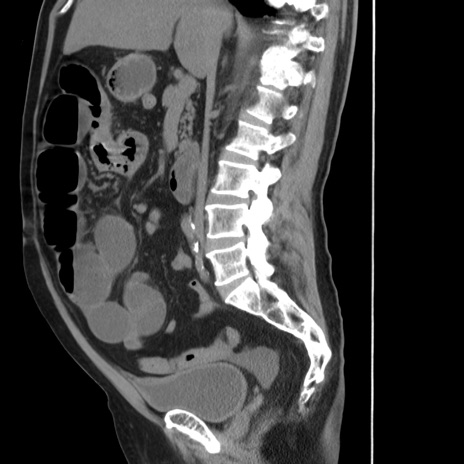

症例20(矢状断像)

【症例】 60歳代男性

【主訴】 腹部膨満、嘔吐

【現病歴】5日前頃より倦怠感を認め食事量減少し4日前の朝嘔吐、食事摂取困難となった。 3日前近医受診し点滴施行され整腸剤などを処方された。 当日他院を受診し、腹部膨満著明、炎症反応の上昇(CRP10.8、WBC11200)あり、紹介受診となる。

【身体所見】 意識JCS1 受け答えがはっきりしないBP 111/57mHg、 P 67bpm、、BT35.2°C、SpO2 97%(RA)、 腹部:膨隆、打診で鼓音あり、全体的に圧痛有り、腸蠕動音(-)、反跳痛ははっきりせず。

【データ】WBC 11400、CRP 14.20